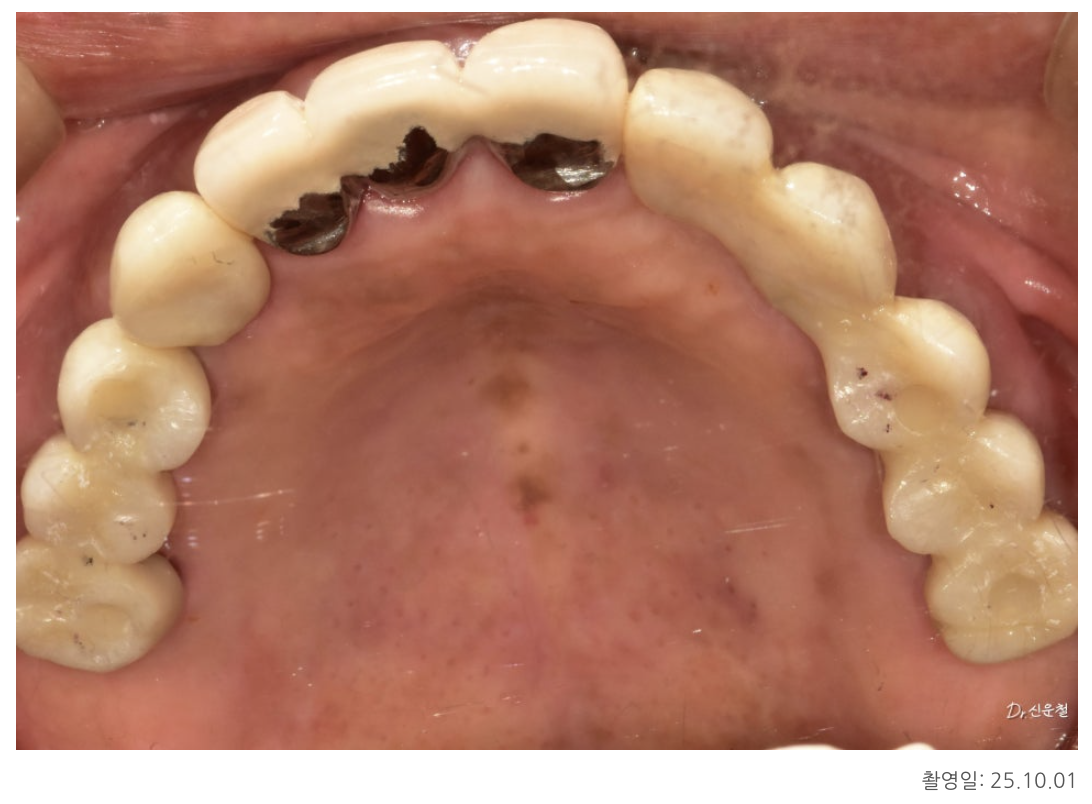

✔ 치료 방향: 총 6개의 임플란트로 기능 회복

치아 기능이 유지되는 아래턱의 범위를 기준으로

위턱 역시 좌우 6개 영역에서 맞춰 균형을 잡았습니다.

즉,

불필요하게 넓히지 않고

힘을 안전하게 지지할 수 있는 최소 범위만 복원했습니다.

[오른쪽 치료 과정]

4개 상실 → 임플란트 3개로 복원

오른쪽은 치아가 4개 연속으로 빠져 있었습니다.

하지만 이를 한 번에 길게 연결하면

힘이 집중되어 오래 버티기 어렵습니다.

그래서

✔ 뒤쪽 힘이 안정적인 두 자리에만 임플란트를 식립

✔ 3개 치아 역할을 할 수 있도록 다리 구조로 제작

했습니다.

남은 앞쪽 1개는 단독 임플란트로 자연스럽게 회복했습니다.

5개 상실 → 안정된 3개로 복원

왼쪽은 앞쪽부터 뒤쪽까지 총 5개가 빠져 있었습니다.

한 줄 길게 만들면

양 끝에서 서로 잡아당기는 힘 때문에 오래 버티기 힘들기 때문에

오른쪽과 동일하게

✔ 튼튼한 두 곳에만 임플란트 식립

✔ 그 사이 치아는 자연스럽게 연결하여 3개 회복